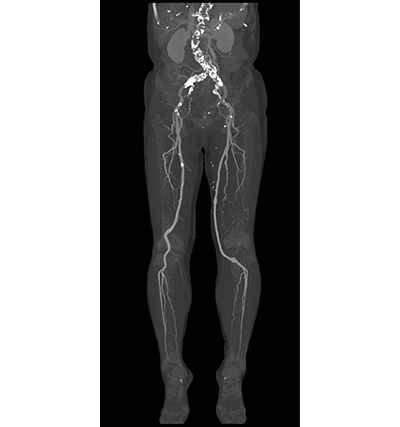

Aquilion Lightning / Helios i Editionでは、腹部造影3相撮影(図2)や下肢の血管撮影など広範囲撮影を行っても、管球冷却待ち時間などが発生せず連続した検査が行える。小林統括SMは、「多くのCT検査をコンスタントに行い、検査内容も耳鼻科の中内耳撮影、頭部CTAなどの頭頸部から下肢CTAまでさまざまです。患者さんをお待たせすることなく、効率的に検査を進めるためにも、余裕を持って検査を行えることは助かります」と述べる。下肢CTAではAiCE-iを適用することでノイズが低減し、高分解能の画像データが得られるため、骨と血管の分離が容易になり、3Dワークステーション(WS)を使わずに本体のコンソールで3D作成を行っている(図3)。関根マネージャーは、「3DWSにデータを転送する必要がなく、検査のスループットが向上しています」と述べる。

図3 CTコンソールにて作成した下肢CTA 3D画像